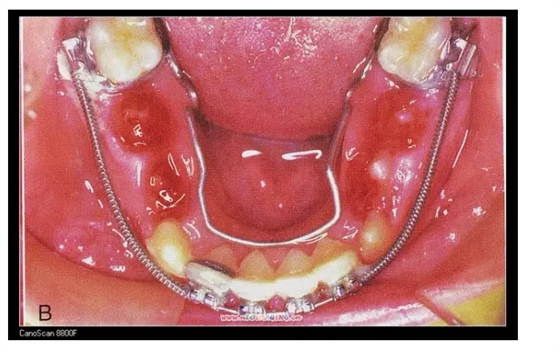

三、擴(kuò)弓器

很多牙列不齊常伴隨牙弓過(guò)窄,所以擴(kuò)弓器是正畸醫(yī)生的好伙伴,它可以以多種形態(tài)和您見面。